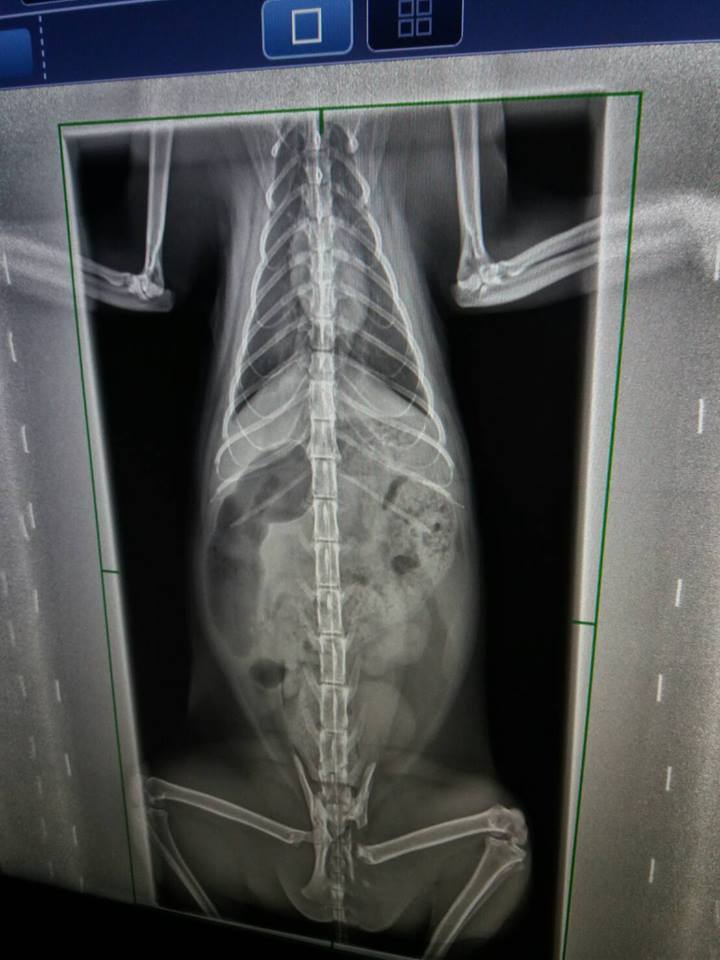

主題: 骨盆腔狹小進行灌腸與追蹤治療的艾咪 申請者姓名: 臺北市支持流浪貓絕育計劃協會 花色: 申請日期: 2017-06-15 11:28:56 申請者部落格: 申請者臉書網址: 所在縣市/合作醫院: 台北市/澄諾動物醫院 治療費用: 6300元 需求人數: 15人 已結案 (2024-06-01 13:27:02) 報名人員: 海郁(已付款)、ocean(已付款)、琪芳(已付款)、林妮妮(已付款)、COCO(已付款)、Jin(已付款)、Karen Chiou x2(已付款)、Tsai Dobbie x2(已付款)、meemee(已付款)、貓步小姐(已付款)、yushi0304 x3(已付款)、 候補人員: 動物病情說明: 因骨盆與腿部骨折而導致骨盆狹小的艾咪,

4/27 澄諾回診 艾咪 3.21KG

【回診狀況】

艾咪又連續沒大便因而再度回診,

X光下發現大腸寬度變大,

認為有一可能導致艾咪雖有大便但無便意,等到積很久後,

後面大便已乾,

認為杜化液可能對艾咪已無太大效果